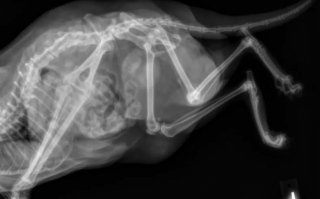

Julia Williford était famille d’accueil temporaire lorsqu’elle a ouvert la porte de son foyer à Leggy Lu, alias Lu. Entre cette féline à la robe blanche tachée de noir et la jeune femme, le courant est tout de suite passé. Le handicap de la chatte a demandé une adaptation particulière car, en effet, Lu avait 5 pattes et de grandes difficultés pour se mouvoir.

Plusieurs fois sur son compte TikTok, la jeune femme originaire du Tennessee (États-Unis), est revenue sur le handicap dont souffrait sa protégée. Elle expliquait que la 5ème patte de la chatte ne fonctionnait pas et donc la freinait dans sa mobilité au quotidien. Toutes les articulations de cette patte demeuraient immobiles, comme « soudées » selon les dires de la maîtresse.

Si l’origine de ce handicap est souvent inconnue, la jeune femme a supposé qu’il s’agissait du résultat d’une exposition à des substances toxiques ou cancérigènes durant la grossesse de la mère. Si elle soulignait qu’il ne s’agissait que de « spéculations », cette explication reste tout à fait probable.